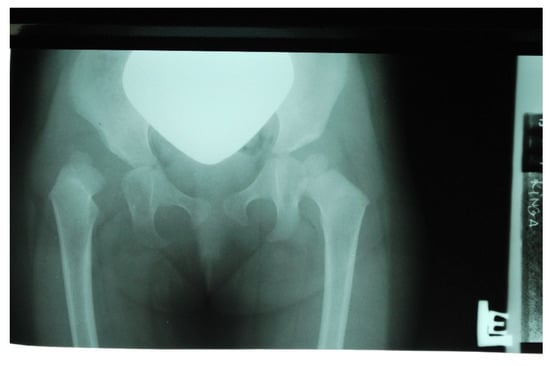

Over time, the parents noticed that the child was very slow to develop motor skills: sitting down and walking. The child did not learn to walk until 22 months of age. While climbing on a slide, the girl always used her lower left limb, without alternating her gait. While walking, she limped on her right lower limb, and reported “right leg pain”. With these observations, the parents again reported to the attending physician, an employee of a private ultrasound lab and national preluxation clinic. Due to the child’s age (24 months), an X-ray of the pelvis was performed, indicating dislocation of the right hip joint (Figure 3).

Figure 3. X-ray scan showing right hip dislocation in the girl (at 2 years of age).